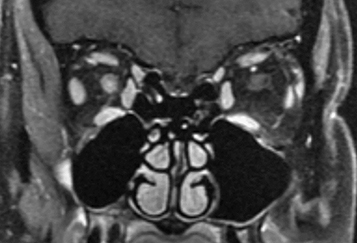

For all cases, MRI of the brain and orbits with gadolinium and fat suppression should be obtained (See Figures 10.14.1 and 10.14.2). While a short segment of optic nerve is involved in typical optic neuritis, lesions in NMOSD may be longitudinally extensive. In addition, patients with NMOSD should have MRI of the spine to look for signs of transverse myelitis. Antibodies for anti-aquaporin 4 (anti-AQP4) and anti-myelin oligodendrocyte glycoprotein (anti-MOG) should be drawn.